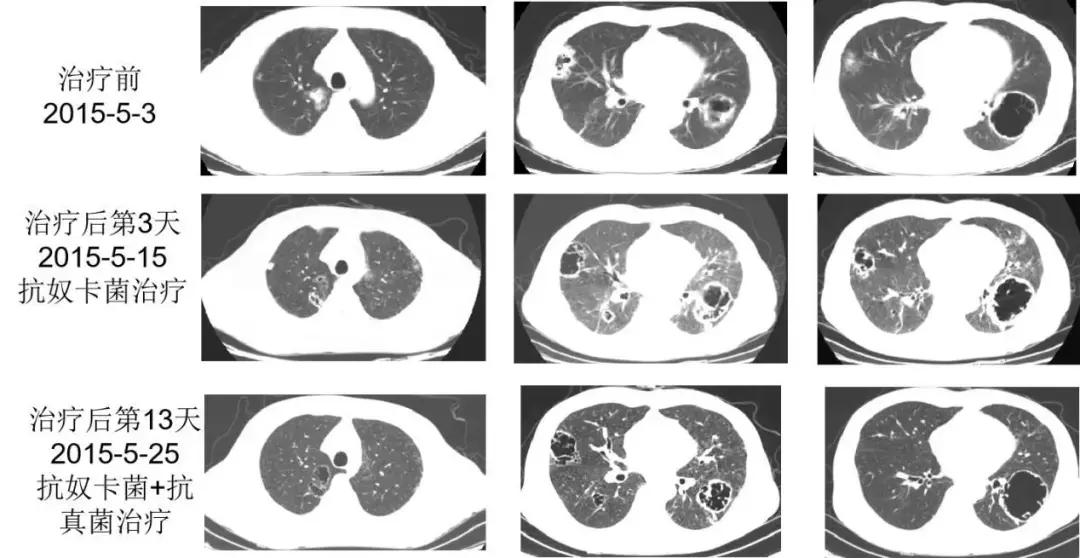

双药联合抗奴卡菌治疗2015-5-13(入院后第7天):复方磺胺甲噁唑 1.44g(磺胺含量1.2g) q6h + 亚胺培南西司他丁 1g q8h;同时经肾内科会诊后调整免疫抑制用药: 2015-5-13(入院后第7天)停用他克莫司,甲泼尼龙改为32mg qd,并每3~5日减4mg,至20mg qd。

2015-5-15(入院后第9天)抗奴卡菌治疗第3天,患者诉右侧胸痛较前有所缓解,但感呼吸困难,咳嗽、咳痰好转不明显,查体:双肺散在哮鸣音,血气分析(吸氧2L/min):pH 7.48,PaO2 60.3mmHg,PaCO2 28.8mmHg,HCO3- 21.7mmol/L。

2015-5-16(入院后第10天)抗奴卡菌治疗第4天,继续复方磺胺甲噁唑 1.44g q6h+亚胺培南西司他丁 1g q8h抗奴卡菌,并加用伏立康唑 200mg q12h抗真菌治疗(首剂400mg)。

转归

患者症状明显好转,血气分析恢复正常,胸部CT双肺空洞较前好转,于2015-5-29安排患者出院。出院带药:复方磺胺甲噁唑 1.44g q6h、伏立康唑 200mg bid、甲泼尼龙20mg qd,出院后予伏立康唑治疗2周后患者自行停药(抗真菌治疗共3周余),继续复方磺胺甲噁唑 1.44g q6h+甲泼尼龙20mg qd治疗。